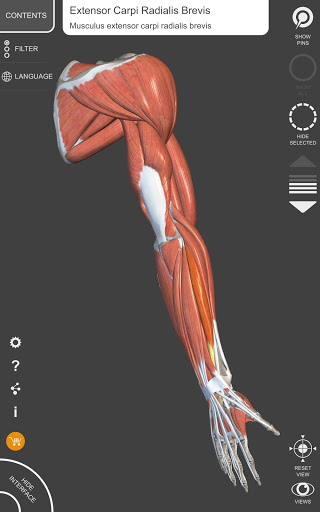

"Anatomy 3D Atlas" memungkinkan Anda mempelajari anatomi manusia dengan cara yang mudah dan interaktif.

Melalui antarmuka yang sederhana dan intuitif, Anda dapat mengamati setiap struktur anatomi dari sudut mana pun.

Model 3D anatomi sangat terperinci dan memiliki tekstur hingga resolusi 4k.

MODEL ANATOMI 3D

• Sistem muskuloskeletal

saraf • Sistem pernapasan • Sistem pencernaan • Sistem urogenital (pria dan wanita) • Sistem endokrin • Sistem limfatik • Sistem mata dan telinga FITUR • Antarmuka yang sederhana dan intuitif • Putar dan perbesar setiap model dalam ruang 3D • Opsi untuk menyembunyikan atau mengisolasi satu atau beberapa model yang dipilih • Filter untuk menyembunyikan atau menampilkan setiap sistem • Fungsi pencarian untuk menemukan setiap bagian anatomi dengan mudah • Fungsi penanda untuk menyimpan tampilan khusus • Rotasi cerdas yang menggerakkan pusat rotasi secara otomatis • Fungsi transparansi • Visualisasi otot melalui tingkat lapisan dari yang superfisial hingga yang terdalam • Dengan memilih model atau pin, istilah anatomi terkait akan muncul • Deskripsi otot: asal, • Tampilkan/ Sembunyikan antarmuka UI (sangat berguna dengan layar kecil) MULTIBAHASA • Istilah anatomi dan antarmuka pengguna tersedia dalam 11 bahasa: Latin, Inggris, Prancis, Jerman, Italia, Portugis, Turki, Rusia, Spanyol, Mandarin, Jepang, dan Korea • Istilah anatomi dapat ditampilkan dalam dua bahasa secara bersamaan PERSYARATAN SISTEM • Android 8.0 atau yang lebih baru, perangkat dengan RAM minimal 3GB Reversi